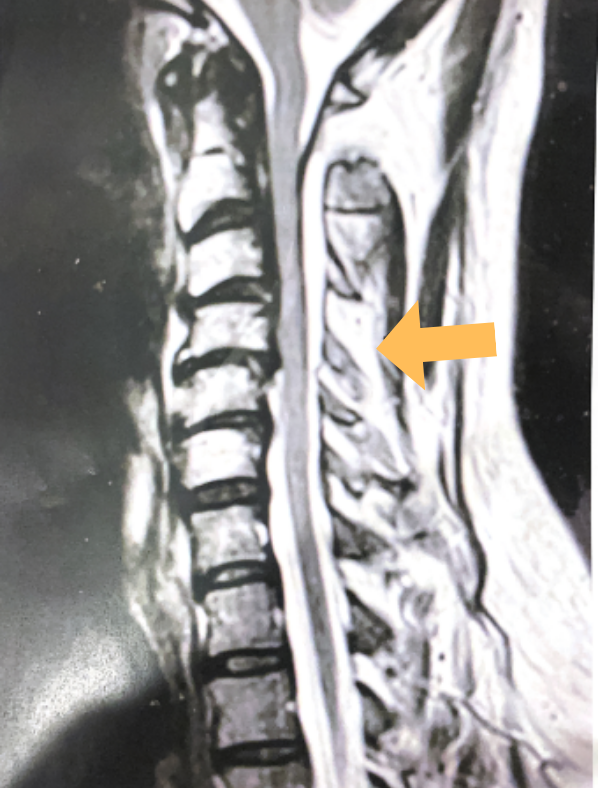

It was felt that the patient was unstable and the patient had signs of early cervical myelopathy secondary to spinal cord compression. The patient consented to undergo exploration and evacuation of the collection and to decompress and stabilize the cervical spine. Upon laminectomy we noticed a ruptured C3-4 interspinous ligament that was consistent with the preoperative imaging studies. After revealing the epidural space during the laminectomy, a large dorsal membrane or pseudomeningocele was noted above a clear fluid collection that was posterior to the dura that was compressing the spinal cord. This membrane was fenestrated and we evacuated the collection which was consistent with CSF. Also during the course of the laminectomy we noted that the source of the CSF leak to be on the left at the takeoff of the C4 nerve root for which the dural sleeve was “degloved” but the fascicles were intact. We repaired with muscle and dural sealants. We completed a C2-C7 laminectomy. The patient had an additional fusion C3-C6 with segmental instrumentation to prevent kyphotic deformity.

(3) Post operative AP and lateral cervical x-ray demonstrating good placement of hardware and alignment.

Patient did well from surgery with reduced pain in left shoulder and no further leak.(Fig. 3)